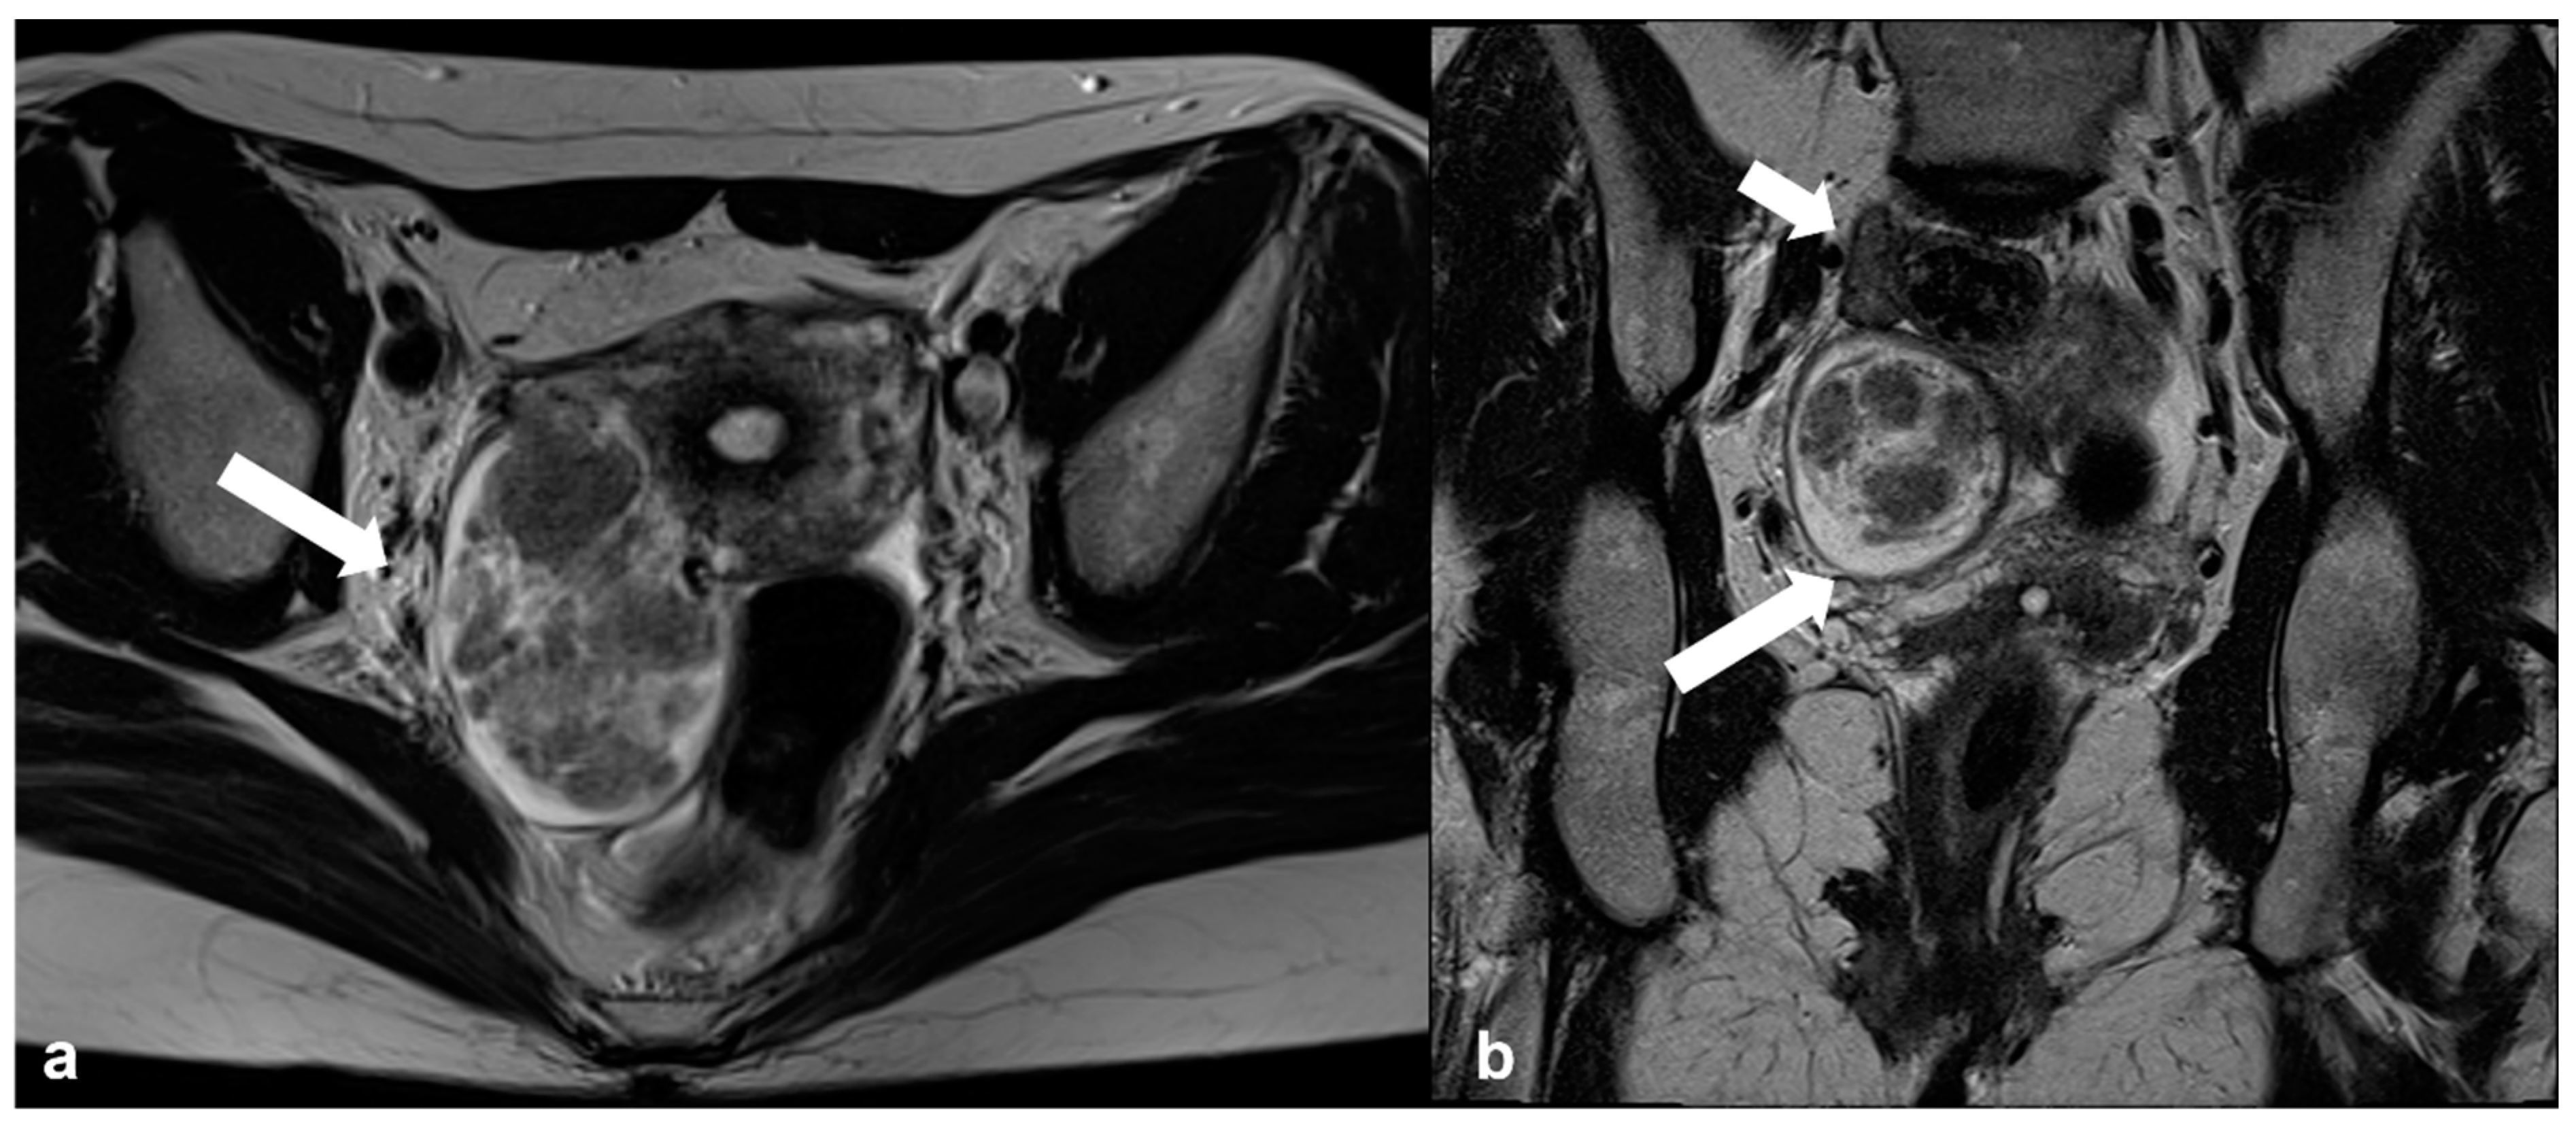

2.1.4. Endometrioid Carcinoma and Clear Cell Carcinoma

2.2. Benign Tumors That Can Mimic EOC